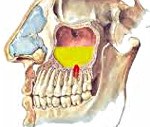

Патогенез одонтогенного гайморита связан с распространением бактериальной микрофлоры и продуктов ее жизнедеятельности (токсинов) в полость гайморовой пазухи из первичных очагов инфекции - пораженных зубов или очагов в верхней челюсти. Это становится возможным из-за особенностей строения альвеолярных отростков 6 и 7 (в редких случаях - 5 и 8) верхних зубов, которые отграничены от синуса только конкой костной стенкой. В результате гнойного расплавления или механической перфорации перегородки инфекционные агенты проникают в полость синуса и вызывают воспаление слизистых оболочек.